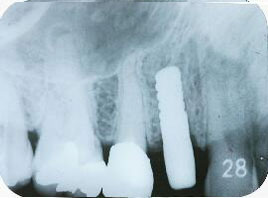

インプラント埋入後1ヵ月のエックス線写真

埋入直後と比べインプラント体頸部の骨の状態が安定してきた

2ヵ月後のエックス線写真